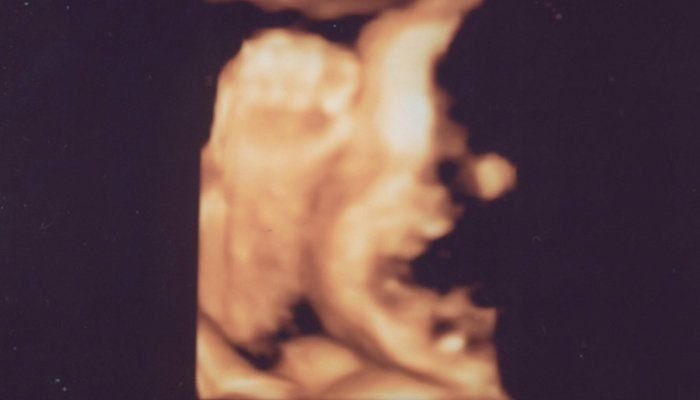

はやしなおさんの妊娠34週目のエコー写真 妊婦生活いよいよラストスパート!

どうやらおなかの赤ちゃんには、すでに髪の毛がしっかり生えているようで、眉毛もうっすら写っています。頭の髪の毛は黒々して、もう伸びているようにも見えます。頬の肉付きもだいぶ良くなり、顔全体がふっくらしています。この時点で推定体重は2500gを超えており、「少し大きい子だね」と言われていました。長女が2600g代で産まれてきているので、すでに近いサイズの赤ちゃんがおなかにいるのかと思うと、いよいよだと少し緊張しました。

エコー中も手を顔の近くでよく動かしており、顔の一部が手で隠れて黒くなっています。口も少し開いているようです。

足回りの骨もしっかり太くなり、だいぶがっちりしてきた印象です。私は以前貧血で鉄剤を処方されていましたが、今回の血液検査では正常。これで安心して出産に臨めると思いました。出産まで、あと残り1カ月ちょっとになり、次第に「長女の一人っ子生活も間もなく終わってしまう」と寂しさを感じるようになって、娘との時間を大切にしたいと感じていました。妊娠後期に入り無理はできませんでしたが、近場でたくさんお出かけをして娘との時間を惜しむように過ごしていました。